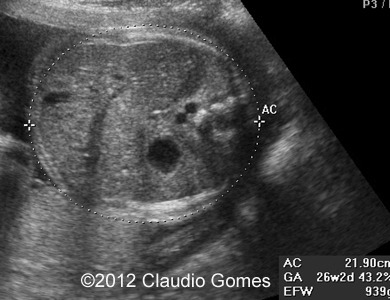

Images 4, 5: 26 weeks-Persistent right umbilical vein and again a vessel posterior and to the right of the aorta (Azygos vein).

f2

Fig5